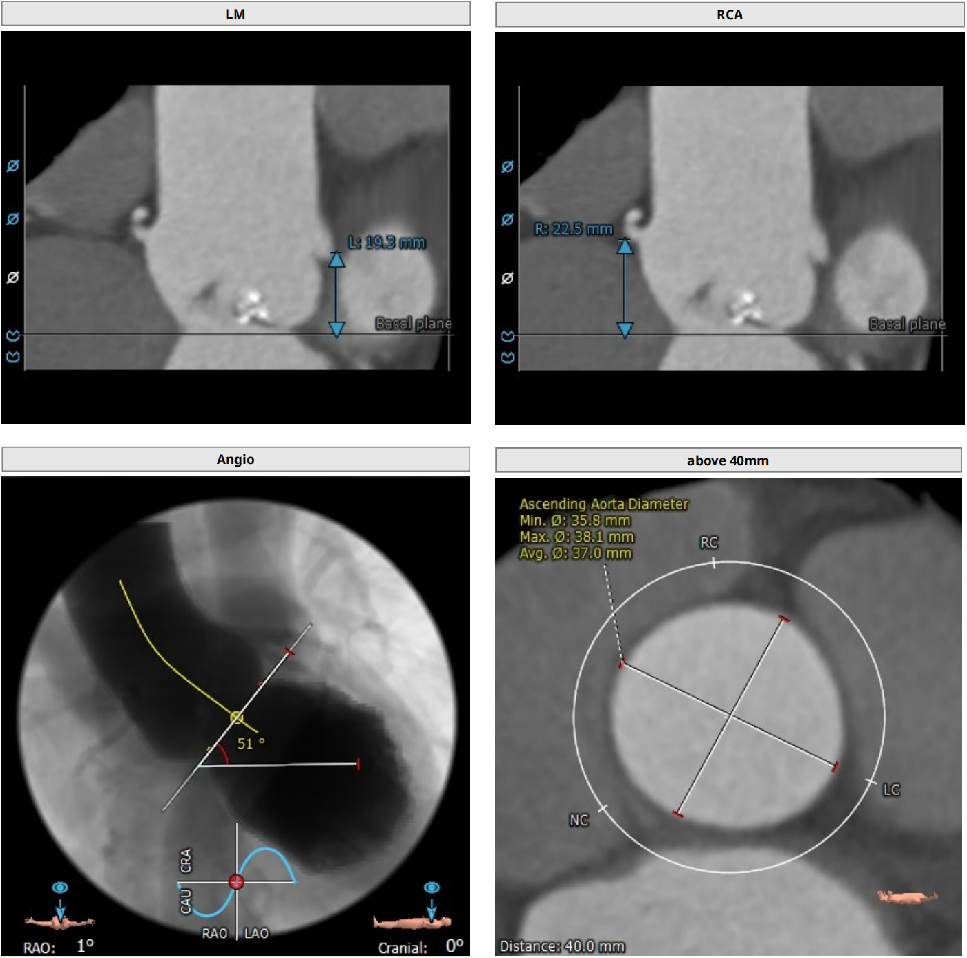

病例二

type0型二叶瓣,中度钙化

Annulus:27mm

LVOT:31.7mm

STJ:33.6mm

升主动脉:37mm

LM:19.3mm

RM:22.5mm

CT分析

Anulus 27,LVOT 34.2,短径25.9,STJ高度可,初步预估32/29瓣膜。

窦部短径26mm、左右冠空间足够,冠脉高度可心脏角度51°、升主未增宽。

体位:LAO 4° CRA 7° ;type0型二叶瓣一个角度即可,有需要可测cusp-overlap角度;轻度钙化,位于瓣叶游离缘,基本不影响瓣膜位置。

心尖薄,导丝塑性需注意形态,入路可,右股做为主入路。

预装32瓣膜,25球囊扩